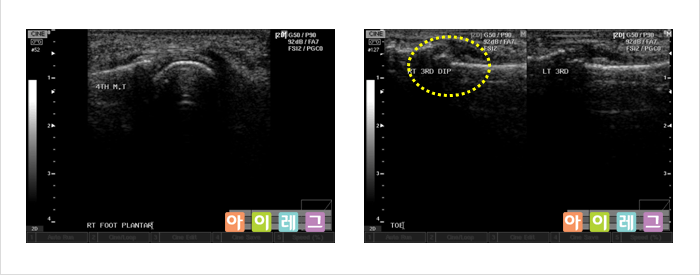

근골격계 초음파는 비전리 방사선의 한 종류인 초음파를 이용하여 영상을 만들어 냅니다. 초음파는

환자에 미치는 통증이나 방사선 노출이 전혀 없는 안전한 검사방법으로 관절,

연골, 인대, 건(힘줄), 점액낭, 근육, 신경 등 우리 몸을 움직이는 근골격계 구조물들의

이상(물이 차거나 염증 혹은 손상이 생긴 경우)을 진단하는 검사입니다. 환자의 진찰과

동시에 간편하게 시행할 수 있고, X-ray 등 방사선

검사로서 확인할 수 없는 경우 진단이나 치료에 도움이 됩니다.

또한, 근관절 정밀영상에 이용되는 고가의 MRI(자기공명영상)검사에 비해

저렴한 비용으로 시행할 수 있다는 장점이 있습니다.

* 위 영상은 모두 아이레그 의원에서 직접 검사한 영상 입니다.